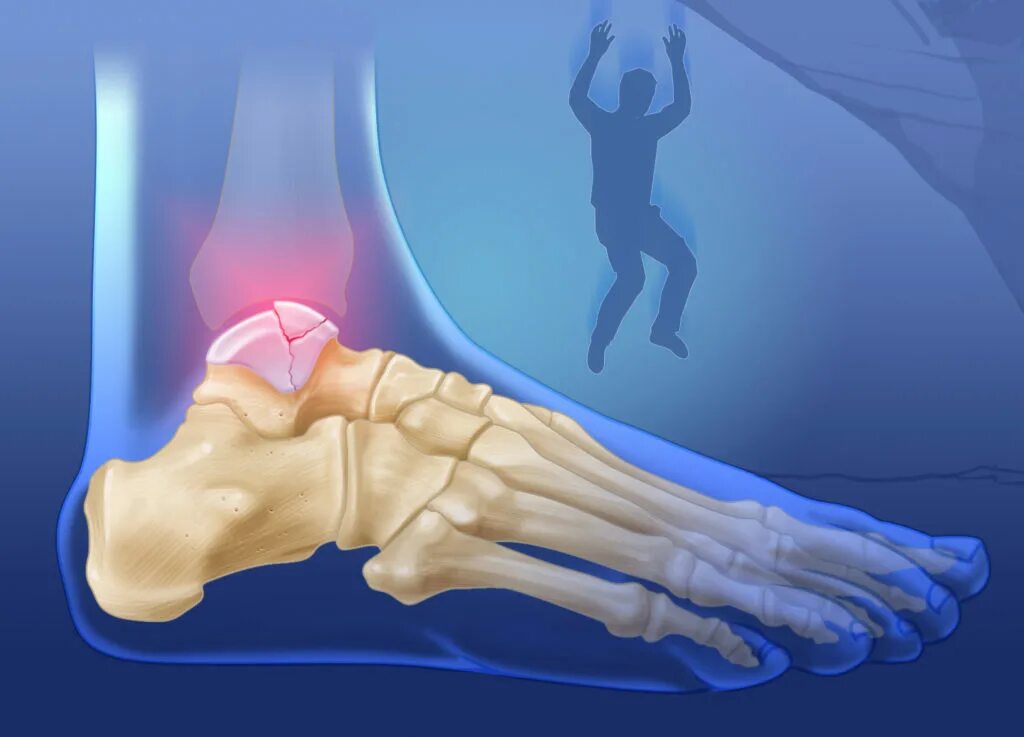

Открытые и закрытые вывихи